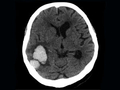

[ISC2017]止血药物或无法阻止脑出血患者的血肿扩大